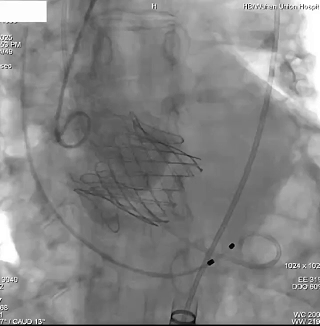

瓣膜功能、形态良好,未见反流